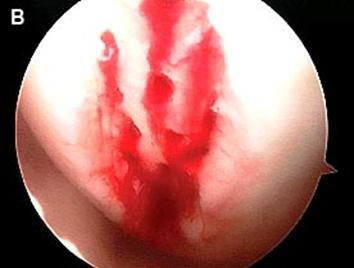

Fig.25.a. Debridarea. Fig.25.b. Microfracturare.

Fig.27. Microfracturi.

Fig.28.

Sange din microfracturi.

Dupa indepartarea cu succes a stratului de cartilaj calcifiat, o andrea este folosita pentru a face mai multe gauri mici (mirofracturi) in osul expus al defectului condral aflate la distanta de 1-2 mm. Trebuie lasata o punte de oase potrivita intre gauri. Tehnica de microfracturi are numeroase avantaje fata de foraj. Mai intai de toate, creaza o leziune termala mai mica. Mai mult, cu microfracturi, chirurgul este capabil sa intre in zonele dificile ale suprafetei articulare cu un control mai bun asupra adancimii de patrundere. La finalizarea microfracturii, o suprafata aspra este generata pentru a aderenta cheagului de sange care contine celule mezenchimale nediferentiate de la osul subcondral. Trebuie avut grija ca cele mai marginase parti ale leziuni sa fie patrunse de andrea pentru a ajuta la vindecarea tesutului reparator la imprejmuirea suprafetei articulare. Odata ce microfractura este finalizata, pompa artroscopica este oprita pentru a se asigura ca sangerarea maduvei curge din gaurile mici umpland defectul.[54]